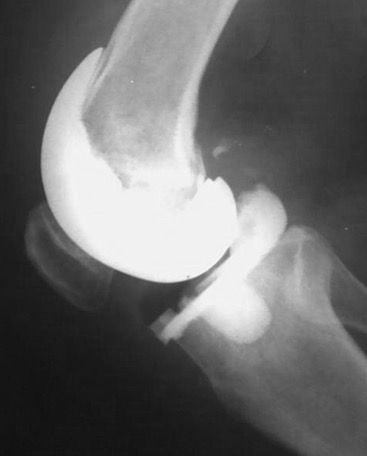

The knee is closed in a standard fashion with one deep drain, which is closed for the first 6 hours. Systemic AB therapy is started in the OR. A long brace which allows flexion is added only if the knee would not be stable enough. X-rays in two layers are performed either intra OR ore before mobilization to confirm proper positioning of the implant (Fig 14)

Final Implantation

After planning and preparing the revision implant with stems, metal blocks, and metaphyseal fixation options the final implantation is done in a standard way as described in a previous study [12]. Although depending on bony defects and ligament situation a primary implant might be possible, we routinely use a revision implant which allows additional stem fixation and higher constraint when needed. “Less constrained possible” is used for the final implantation therefore, our favorite implant is a varus/valgus constrained design which allows the use of a PS insert in balanced knees (Fig 16).

RHK would be used only in knees with insufficient extensor mechanism, global instability, severe bone defects AORI type 3, recurvatum or joint line changes > 8 mm. This is very rare in this scenario with SA knees. Removal of the AB prosthesis should be possible very easy, otherwise the implantation was not done “press fit” (Fig 17).

Own Results

16 consecutive patients with active SA had been treated with a two stage TKA procedure between 2006 and 2016. Mean FU was 6.1 years (range 2.0 to 9.9 years) and no patient was lost for FU. The median number of prior open or arthroscopic debridement before the two-stage procedure was 2 (range 1 to 6). All patients showed clinical and laboratory sign of a septic arthritis with severe chondrolysis or OA. The infection was cured after 6 weeks for all knees. Final implantation was performed between 6 to 12 weeks in all patients with a varus/valgus constraint implant (NexGen LCCK, Zimmer, Warsaw). Only three knees needed a CCK insert, whereas 13 knees were stable enough for using a PS insert only. For the AB spacer and final implantation no intra- or postoperative complications occurred.

No patient needed a brace for mobilization and all patients where highly satisfied with their pain and function in the interval. They reported residual pain only, were able to walk without crutches with good ROM and many of them even ask if the final implantation will be necessary. After final implantation the patients showed comparable outcome to normal primary knees. The mean KSS objective and function score increased significantly from preop situation (58/17) to after spacer implantation (75/46) and further improved after TKA implantation at the final FU (96/86). The mean VAS score was 6.5 preop, decreased to 2.1 after the spacer and 1.2 after TKA at final FU. At final FU no clinical or radiographic signs of infection, loosening or osteolysis could be identified in all patients.